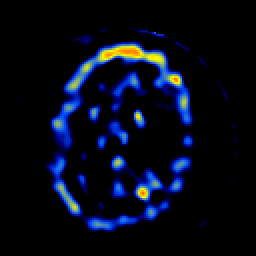

SPECT TL Study #8 -- Slice #43

[Home][Help][Clinical][Tour 1][Tour 2][Tour 3] Slice 43